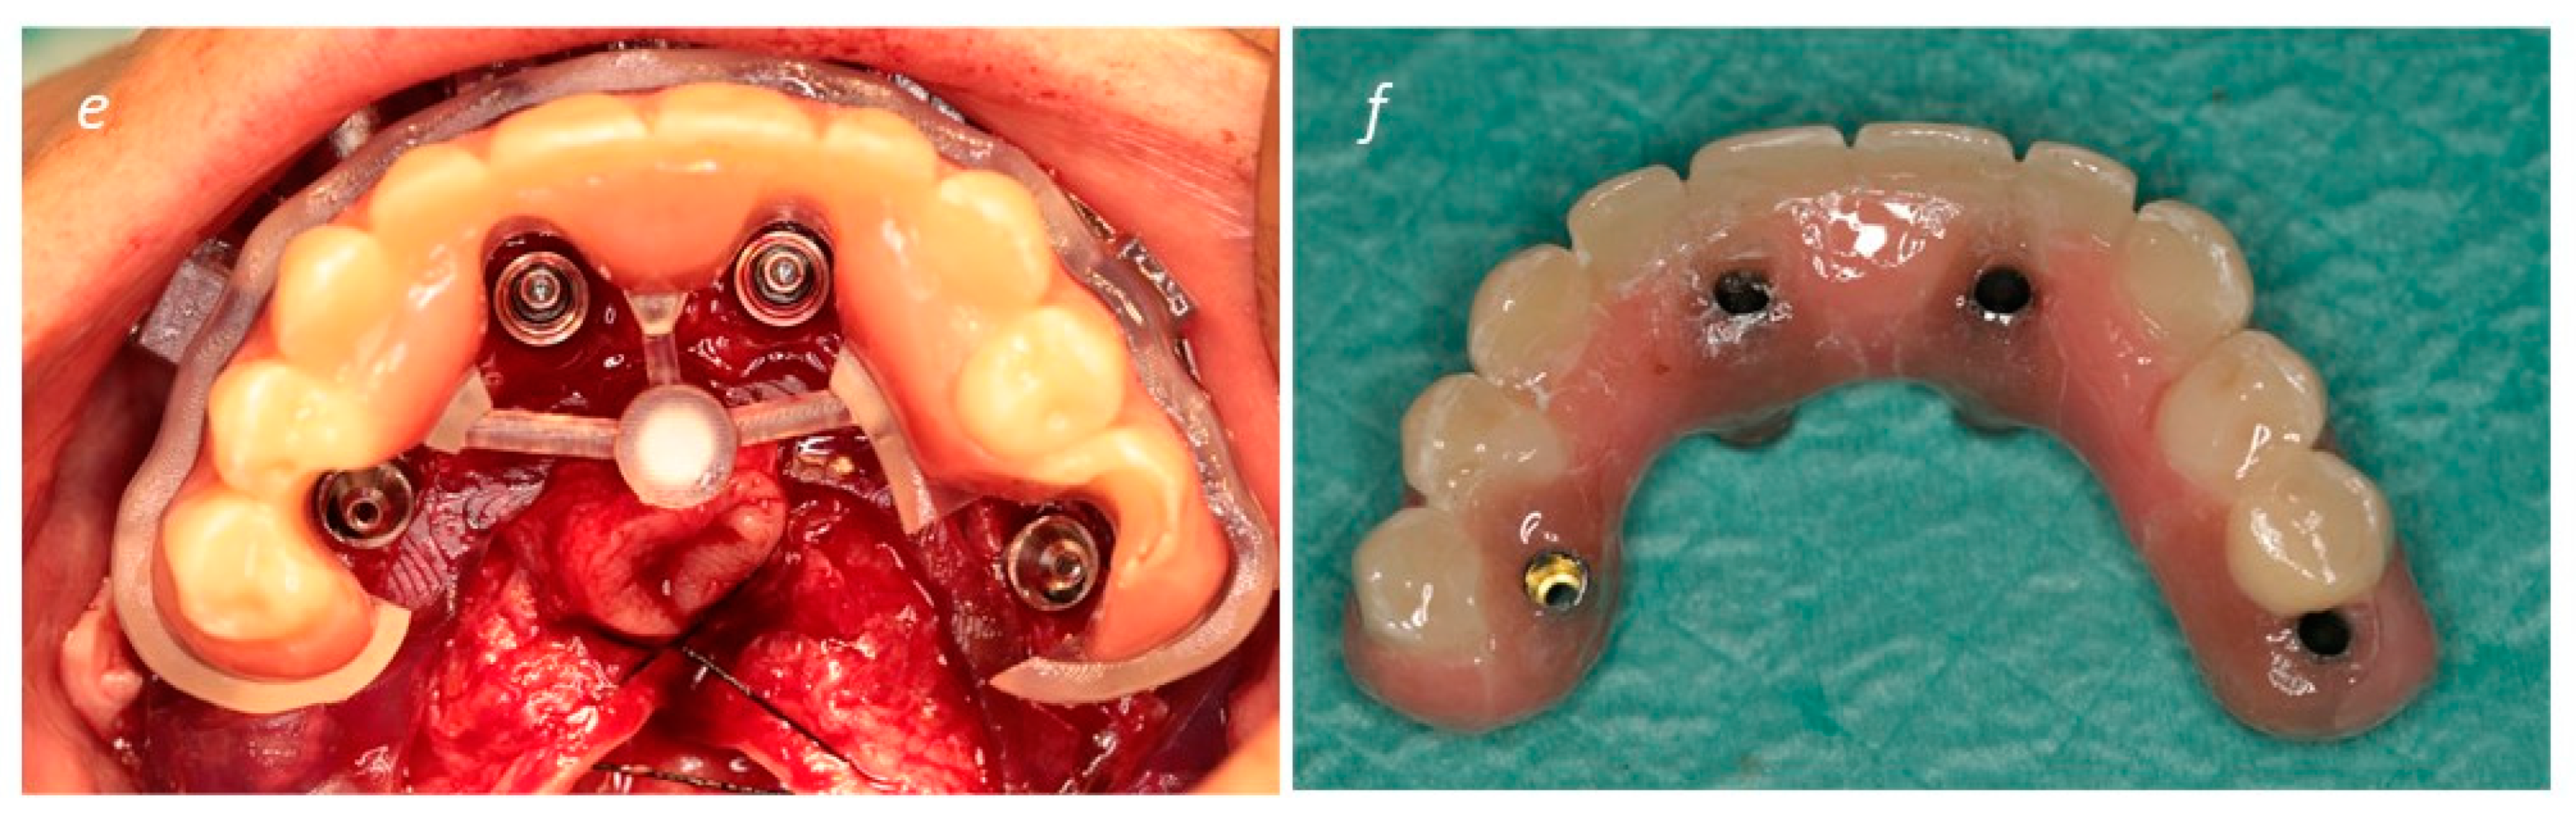

A New Full Digital Workflow for Fixed Prosthetic Rehabilitation of Full-Arch Edentulism Using the All-on-4 Concept

2. Materials and Methods

Description of the Technique

3. Results